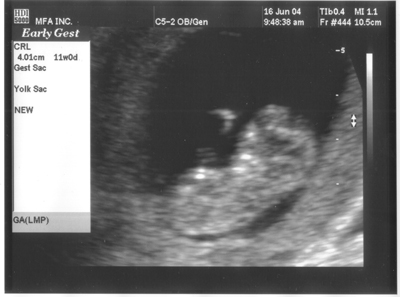

16. Juni 2004